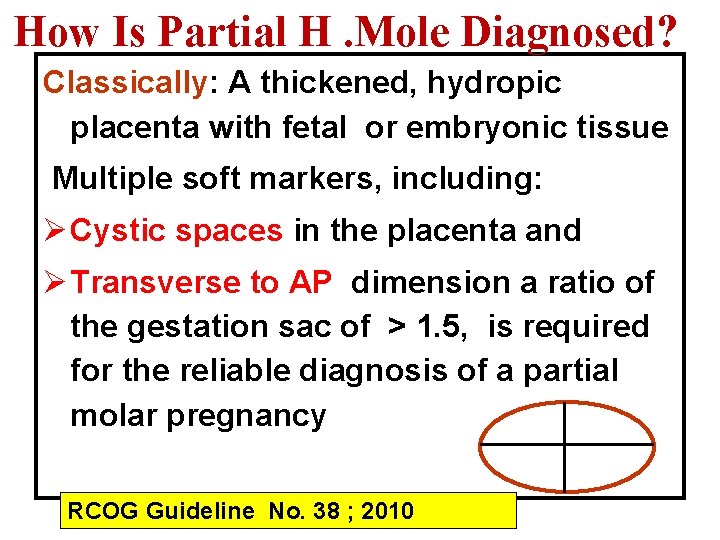

How Is Partial H. Mole Diagnosed? Classically: A thickened, hydropic placenta with fetal or embryonic tissue Multiple soft markers, including: Ø Cystic spaces in the placenta and Ø Transverse to AP dimension a ratio of the gestation sac of > 1. 5, is required for the reliable diagnosis of a partial molar pregnancy RCOG Guideline No. 38 ; 2010